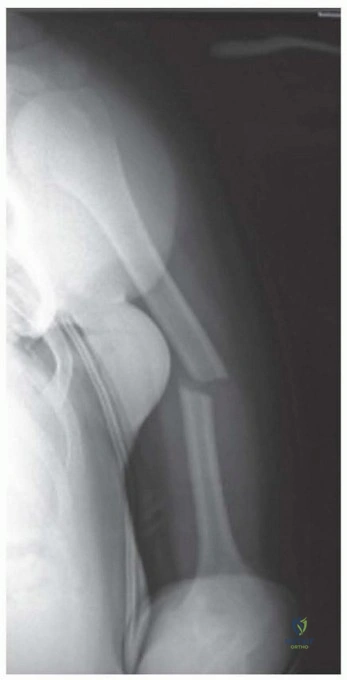

Imaging and Templating

Standard orthogonal radiographs, including an anteroposterior and true lateral of the entire humerus, are mandatory. The imaging must visualize the shoulder and elbow joints to rule out intra-articular extension. Computed tomography is rarely indicated for diaphyseal fractures unless there is suspicion of occult intra-articular extension at the distal humerus.

Digital templating is performed to determine the appropriate plate length. A general biomechanical rule for diaphyseal plating is to achieve a minimum of three to four bicortical screws (six to eight cortices) in both the proximal and distal main fracture fragments. A 4.5 millimeter narrow limited contact dynamic compression plate or locking compression plate is typically selected.

Clinical & Radiographic Imaging